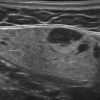

Hạch tuyến nước bọt

» Thông tin: Nữ giới – 66 tuổi.

» Lâm sàng: Sưng đau vùng góc hàm.

# Hạch lành tính ngoại vi tuyến nước bọt dưới hàm.